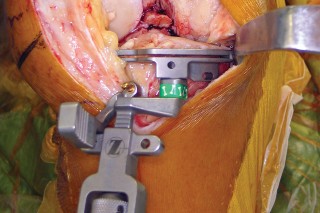

يركز هذا النهج على استخدام فتحة المفصل شبه الرضفية الإنسية المحدودة (Limited Medial Parapatellar Arthrotomy) وشق العضلة الرباعية المحدود، وهو جزء من مجموعة من الأساليب المعدلة التي توفر وصولاً ورؤية محدودين، ولكن يمكن تحويلها إلى نهج تقليدي إذا لزم الأمر. هذا يعني أن الجراح يمكنه البدء بتقنية أقل توغلاً، مع الاحتفاظ بالقدرة على التكيف إذا كانت الحالة تتطلب رؤية أوسع.

يُعد النهج شبه الرضفي الإنسي المحدود في جراحة استبدال مفصل الركبة الكلي بالحد الأدنى من التدخل الجراحي خيارًا مألوفًا ومتعدد الاستخدامات، وقد تطور مع إضافة أدوات أصغر وأكثر كفاءة. يتميز هذا النهج بقدرته على التكيف مع مجال العمليات المحدود في الركبة، مما يسمح بتشريح جراحي محدود دون المساس بالإجراء أو النتائج.

يتمتع الأستاذ الدكتور محمد هطيف بخبرة واسعة في جراحات استبدال مفصل الركبة، وهو ملتزم بتقديم أحدث التقنيات لمرضاه في صنعاء. يحرص الدكتور هطيف على اختيار المرضى المناسبين لهذه التقنية بعناية فائقة، مع الأخذ في الاعتبار جميع العوامل لضمان تحقيق أفضل النتائج الممكنة. إن تركيزه على التفاصيل الدقيقة واستخدامه لأحدث الأدوات يجعله مرجعًا موثوقًا به في هذا المجال.